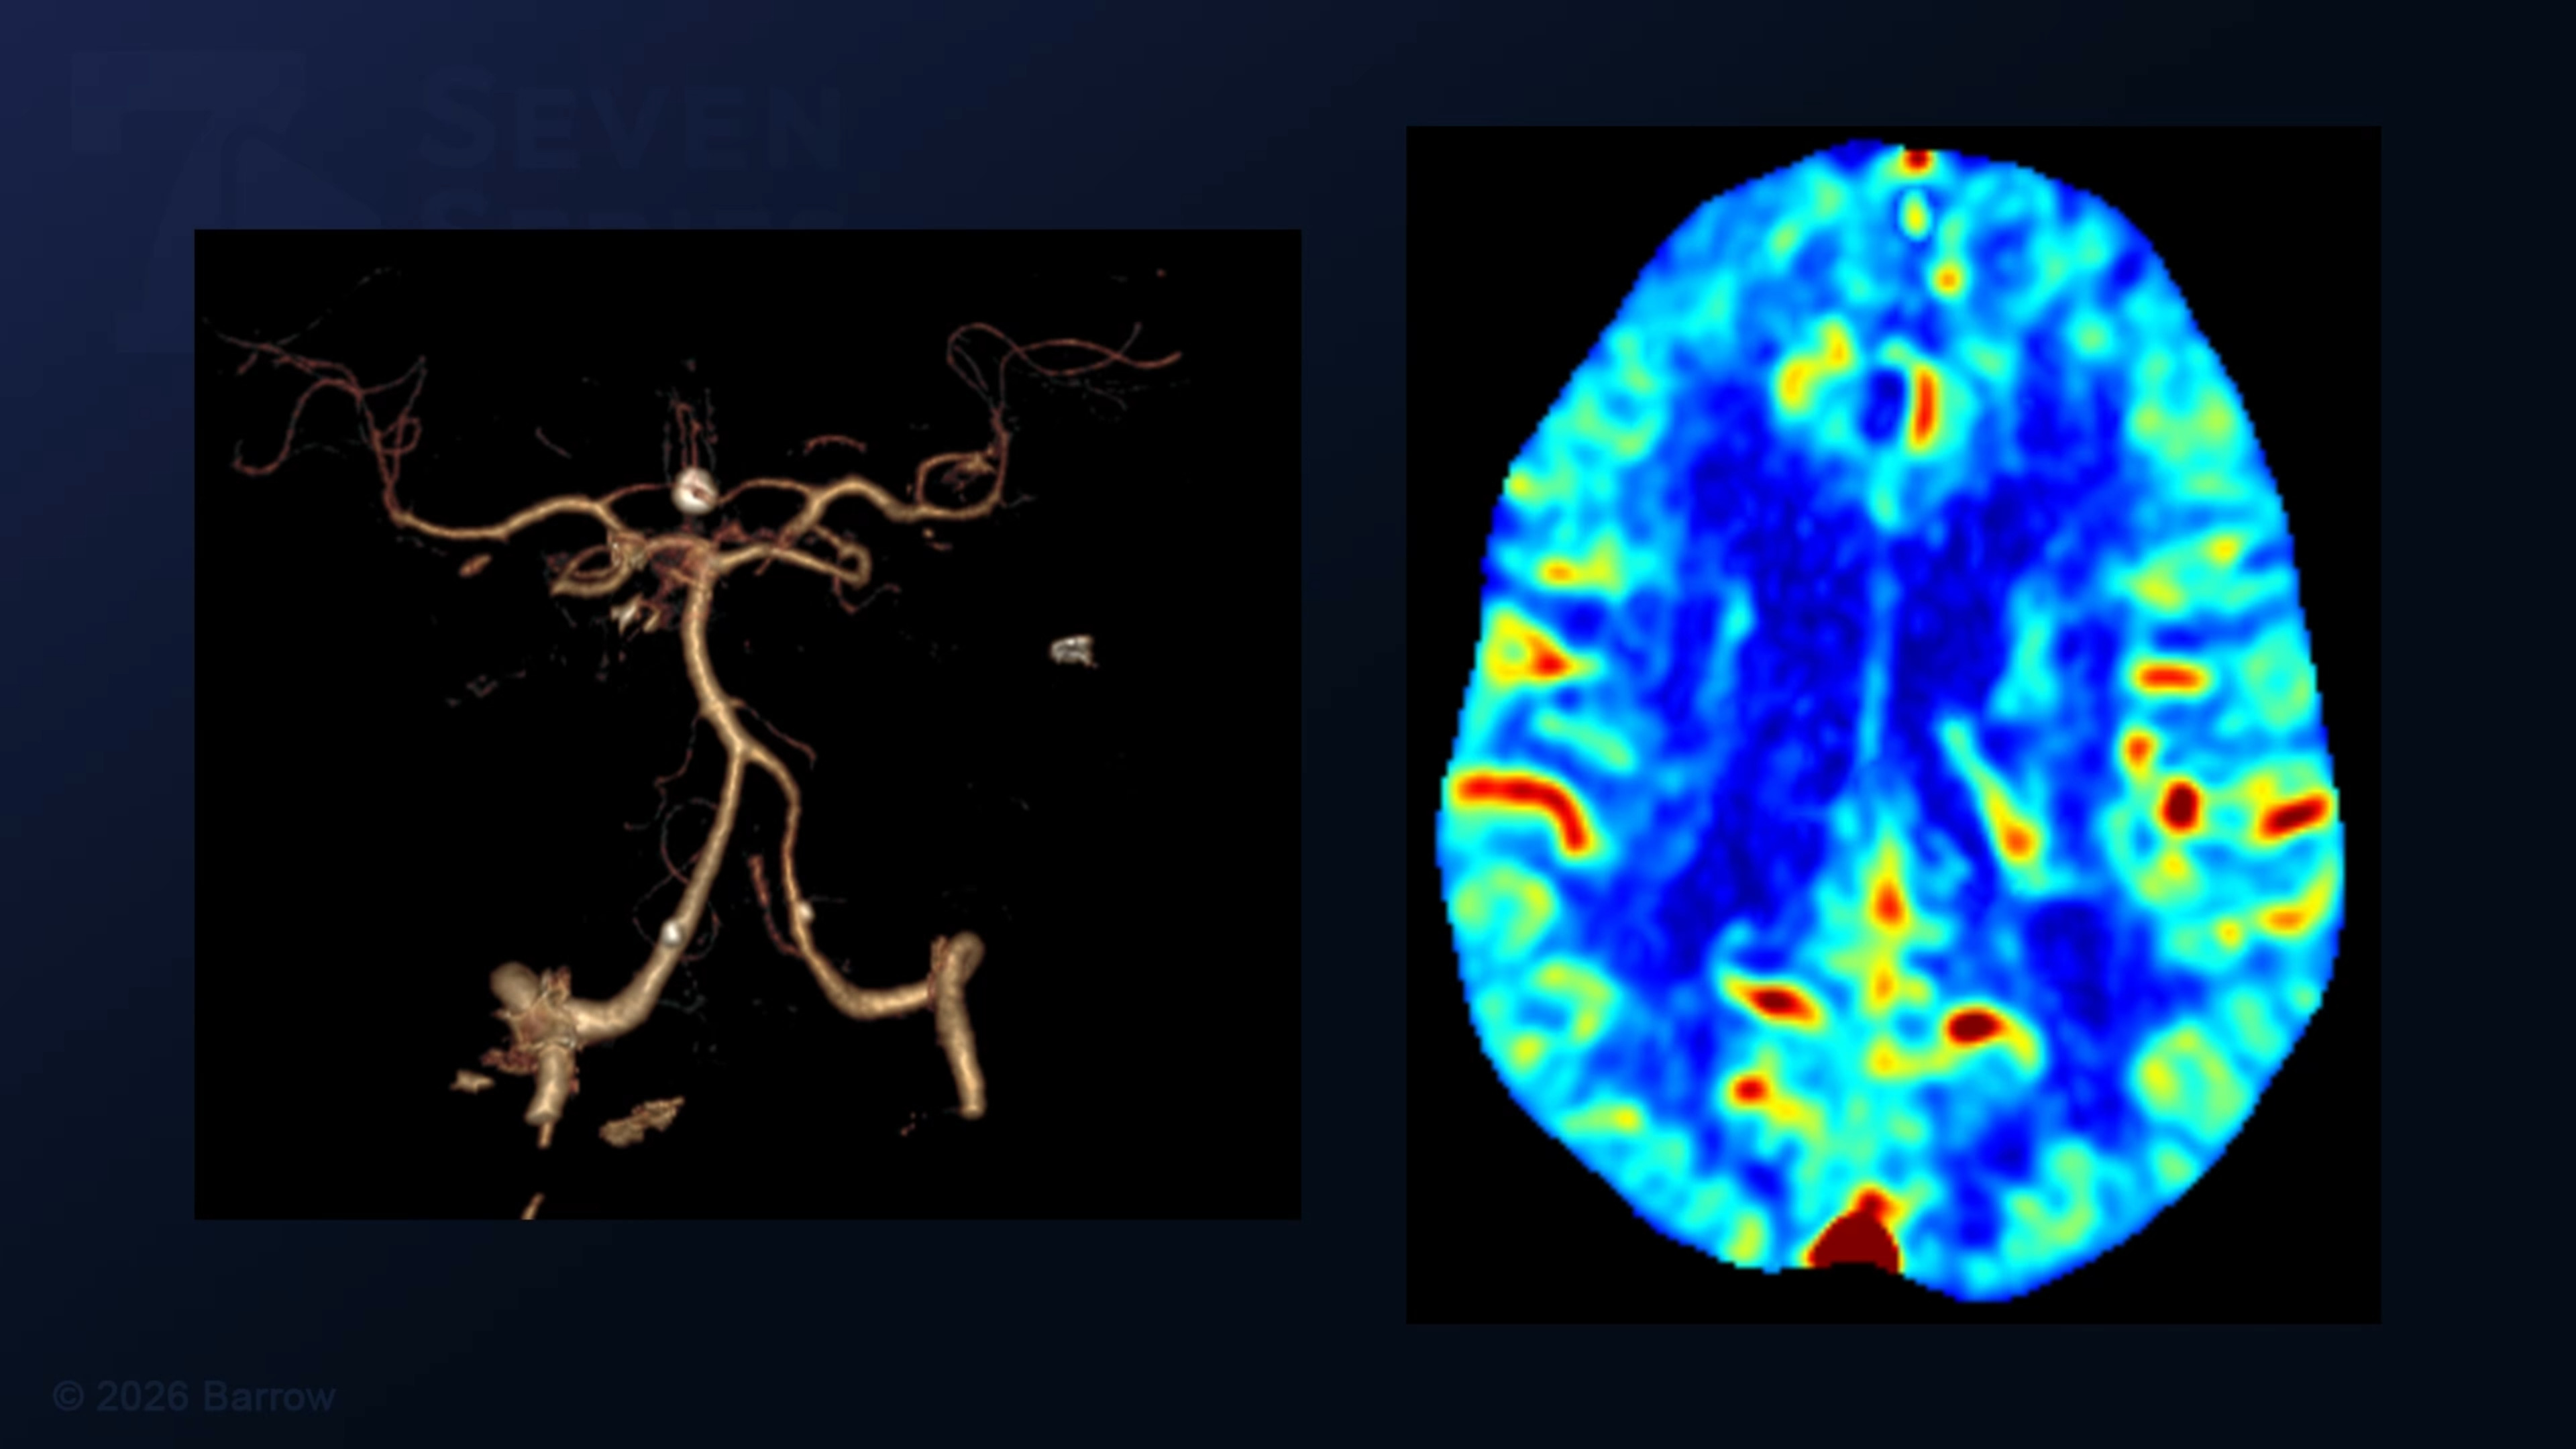

Episode 528 of Seven Series shows a superficial temporal artery (STA) to M4 middle cerebral artery (MCA) bypass for carotid artery occlusion.